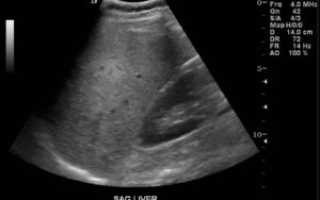

Ультразвуковое исследование (УЗИ)

УЗИ печени позволяет выявить морфологические и структурные изменения органа, такие как:

- Гиперэхогенность – уплотнение тканей.

- Гепатомегалию – увеличение размеров печени.

- Жировую инфильтрацию – скопление веществ, которые в норме отсутствуют.

- Неоднородность плотности органа.